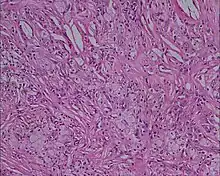

Histology picture of xanthoma showing lipid-laden foam cells with large areas of cholesterol clefts, 10 × magnification, eosin and hematoxylin stain[1]